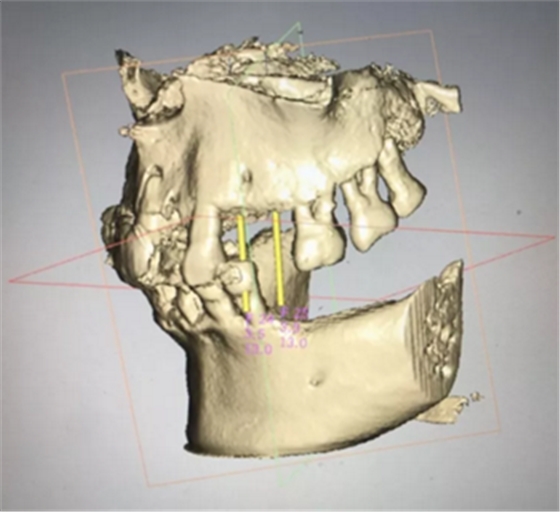

術(shù)前分析,患者上頜骨條件良好。

通過種植導(dǎo)板軟件系統(tǒng)進(jìn)行種植體模擬植入,制定種植手術(shù)方案